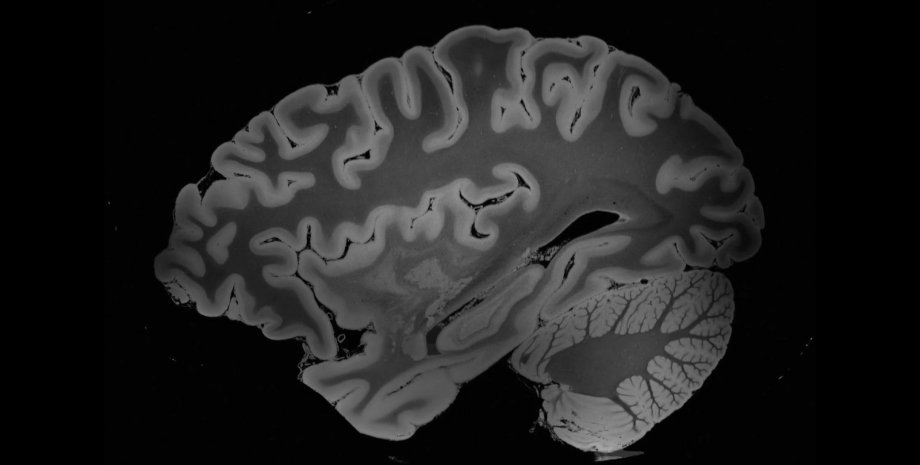

Ученые показали самые детальные изображения мозга человека

С помощью нового МРТ-аппарата удалось визуализировать структуры мозга размером менее 0,1 миллиметра

Биологи из Массачусетской больницы опубликовали самые подробные на сегодняшний день изображения человеческого мозга, полученные в результате 100 часов магнитно-резонансной томографии. Об этом пишет Science Alert.

Исследование проводилось на мозге покойной пациентки, завещавшей свои органы науке. Она умерла в возрасте 58 лет от дыхательной недостаточности, вызванной пневмонией. Психических и неврологических заболеваний пациентка не имела, поэтому структуру ее мозга можно считать обычной для здорового человека.

После консервации орган поместили в специальную воздухонепроницаемую емкость из уретана, разработанную для длительной МРТ-процедуры. Ученые использовали 7-тесловый магнитно-резонансный томограф - мощный аппарат с высоким уровнем напряженности магнитного поля, одобренный для использования в США только в 2017 году. Чем выше напряженность поля, тем лучше общее качество изображения и четче визуализация отдельных структур.

После 100 часов МРТ ученые получили беспрецедентно подробные изображения, где различимы структуры размером всего в 0,1 миллиметра. Исследование пока не опубликовано в рецензируемом журнале, но уже сейчас можно сказать, что оно окажет огромное влияние на изучение человеческого мозга.